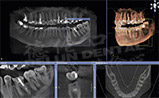

- 德伦口腔斥200余万巨资引进的芬兰全景机,这一台高质量的数字拍片系统。它独有的3D成像技术,层析扫描、电脑设计、科学精准定位,360°旋转,口腔情况一览无遗。芬兰全景机的引入,结束了口腔治疗长期以来依靠医生经验的盲视操作,极大加强了手术安全性、提升手术效果,拉开了广东省口腔治疗的"可视化时代"。